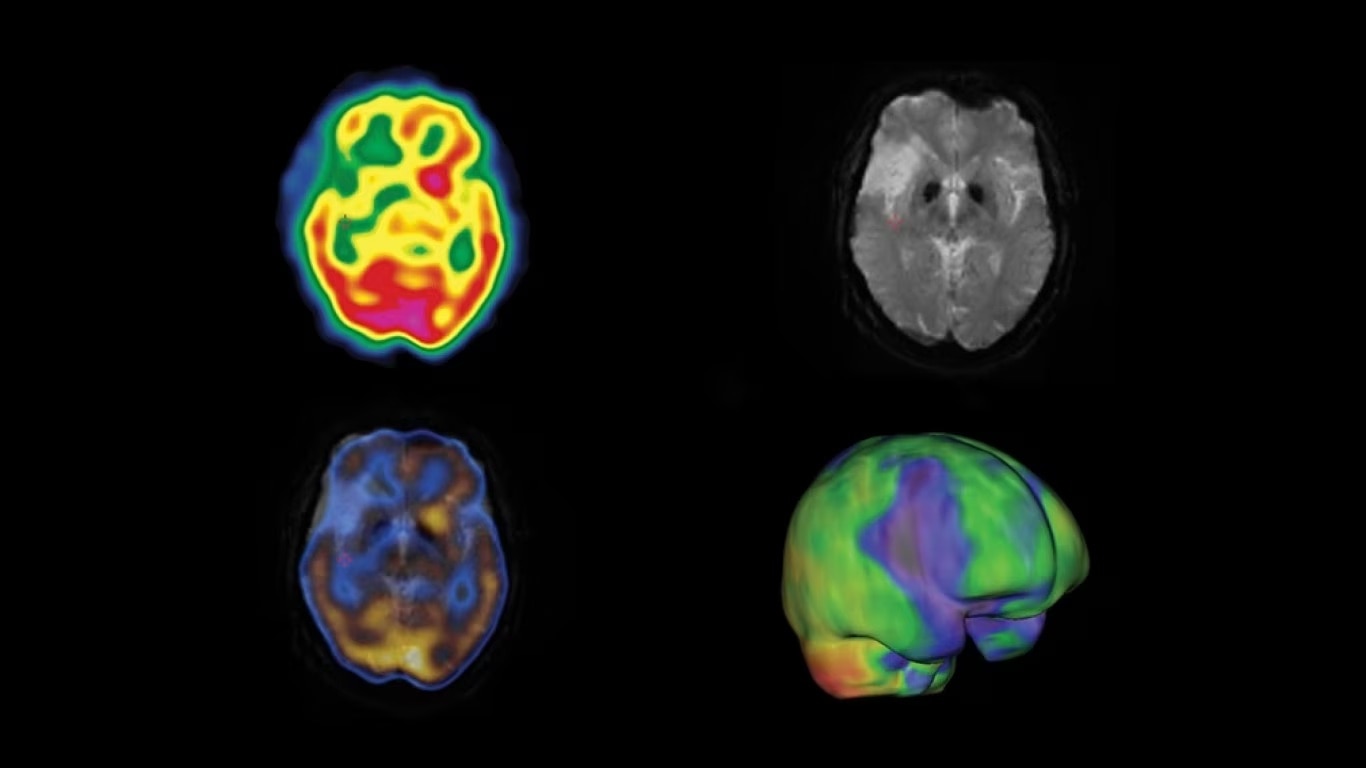

Experience a new productivity hub for hybrid imaging. By automating SPECT/CT reconstruction, SmartConsole simplifies the workflow for complex hybrid and quantitative protocols and allows technologists to review results directly at the scanner console. It also allows physicians to review scans remotely from mobile devices. They can modify processing settings and initiate study processing anytime, anywhere across a LAN or a WAN*.

SmartConsole enables a noticeable improvement in productivity. Now, a physician can provide their input remotely and digitally. For example, physicians can review a whole-body bone scan directly on their tablet or other mobile device and define the scan range limits they need from wherever they are. The time saved with this switch to a digital workflow helps make it possible to complete exams in predictable time slots.